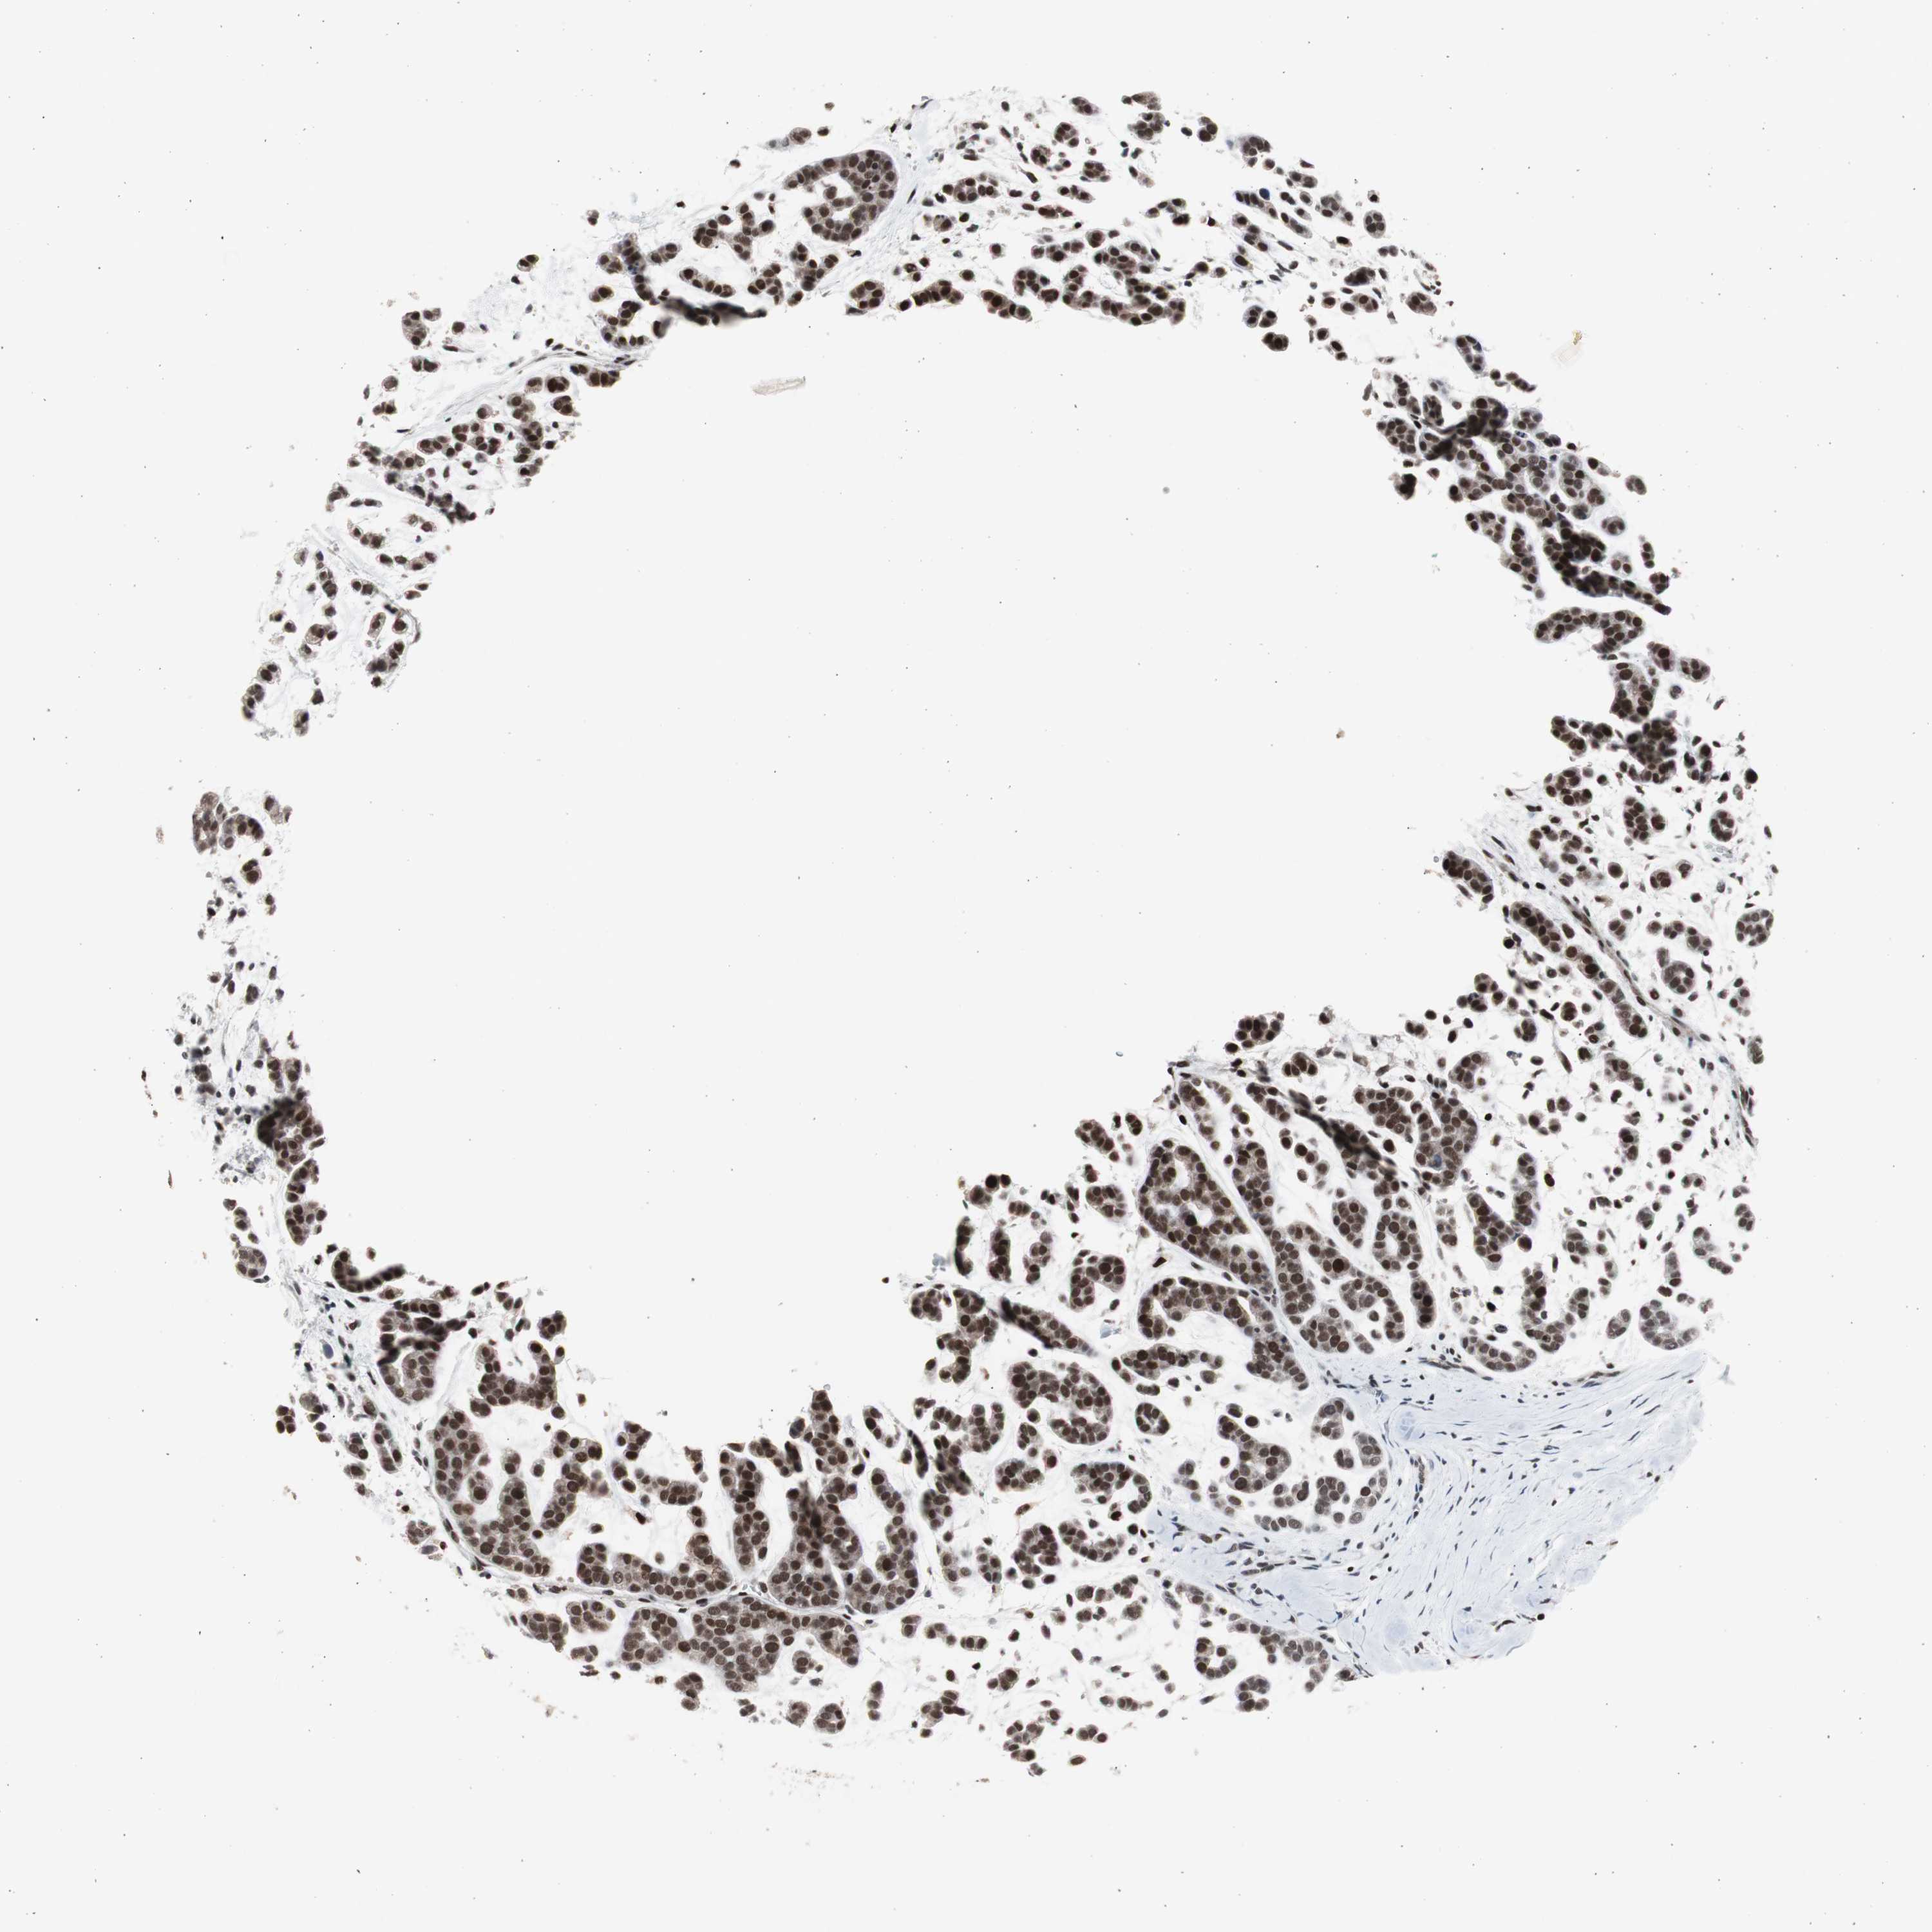

HEAD AND NECK CANCER - Protein expressioni

A mouse-over function shows sample information and annotation data. Click on an image to view it in a full screen mode. Samples can be filtered based on level of antibody staining by selecting one or several of the following categories: high, medium, low and not detected. The assay and annotation is described here.

Antibody stainingi

Antibody staining in the annotated cell types in the current human tissue is reported as not detected, low, medium, or high, based on conventional immunohistochemistry profiling in selected tissues. This score is based on the combination of the staining intensity and fraction of stained cells.

Each image is clickable and will lead to virtual microscopy that enables deeper exploration of all samples and also displays staining intensity scores, fraction scores and subcellular localization as well as patient and tissue information for each sample.

Antibody CAB004563

Staining

High

Medium

Low

Not detected

Intensity

Strong

Moderate

Weak

Negative

Quantity

>75%

75%-25%

<25%

None

Location

Nuclear

Cytoplasmic/membranous

Cytoplasmic/membranous,nuclear

Adenocarcinoma, NOS

Adenoma, NOS

Carcinoma, NOS